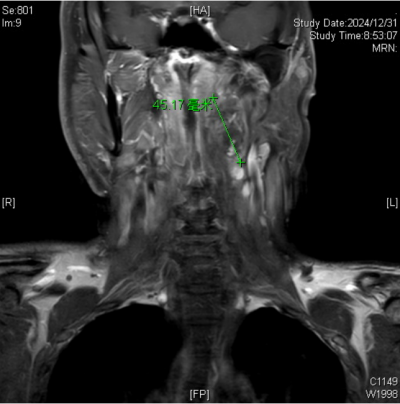

颈部增强磁共振成像(MRI)下发现导致王永元咽部不适的罪魁祸首是咽旁后间隙肿瘤

患者王永元(化名)42岁,来自湖南省浏阳市,一年前感到咽喉不适,自行服药治疗但效果不佳。后到医院检查也并未发现明显异常。但近两个月来,他的咽部异物感逐渐加剧,为了寻求更有效的诊疗,他来到了维多利亚老品牌76696vic(南华大学附属长沙中心医院)的耳鼻咽喉头颈外科就诊。接诊的杨中纯副主任医师通过颈部增强磁共振成像(MRI)检查,最终确诊导致王永元咽部不适的罪魁祸首竟是咽旁后间隙肿瘤,紧邻口咽部。入院后,经过颈部CTA检查,发现肿瘤将颈内动脉推挤至外侧、变形,经过仔细阅片和详细的术前讨论,耳鼻咽喉头颈外科的医生团队制定了周密的手术计划。